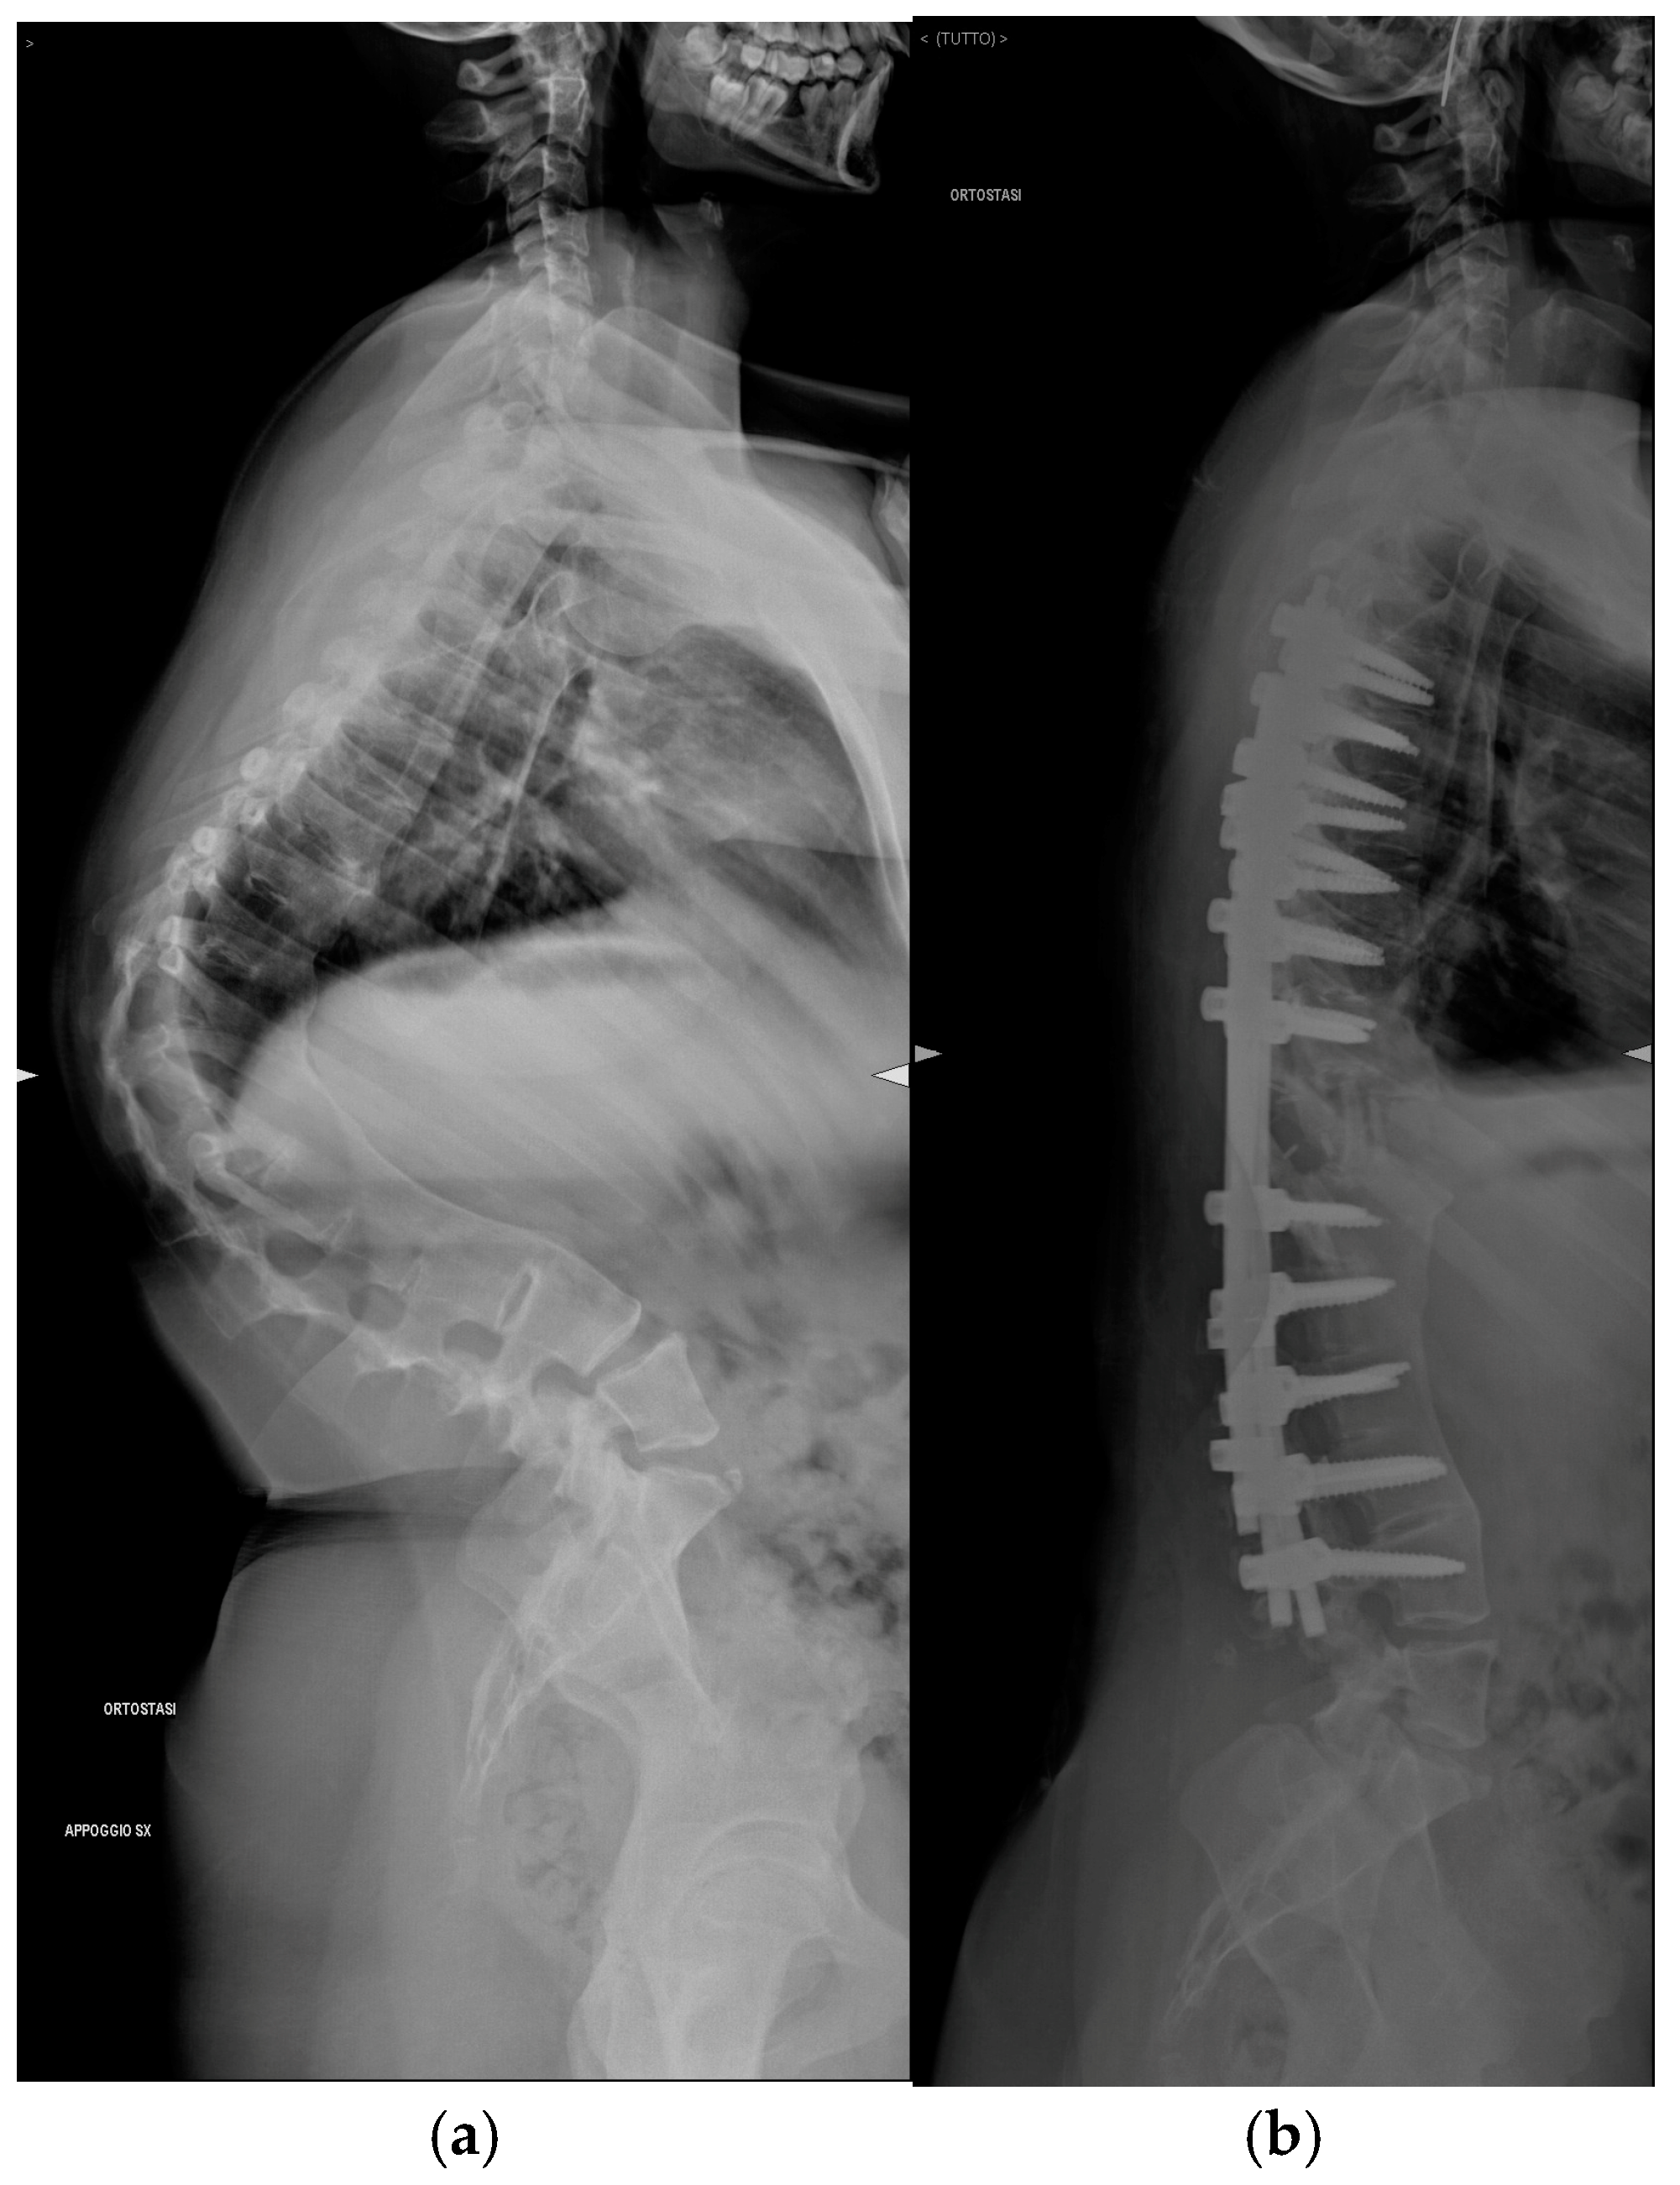

Pre-operative and post-operative radiographs documenting case 5 are reported in Figure 5.

Figure 5. Lateral radiograph of Patient 5. (a) Preoperative assessment. (b) Postoperative assessment.

A 17-year-old female presented with a progressive thoracolumbar kyphotic deformity associated with multiple vertebral fusions. She had undergone conservative treatment during adolescence until her growth was complete. Rheumatological and genetic investigations were negative for specific conditions. Two years prior to admission, she began experiencing thoracic spine pain and difficulty with daily activities, including school-related tasks. More recently, she reported respiratory difficulties both while walking and lying supine.

Postoperative Course

The postoperative course was uneventful. The patient was able to mobilize, achieving independent standing and walking. A thoracic surgery consultant reviewed chest X-rays and a CT scan without contrast, which showed moderate bilateral pleural effusion, but no indication for thoracentesis was given. Preoperative kyphosis measured 88° Cobb, which was reduced to 7° on postoperative radiographs. Preoperative hemoglobin was 12.7 g/dL, and at discharge, following two intraoperative blood transfusions, it was 11.6 g/dL. At the 1 year and 10 months follow-up, the patient was in excellent condition. Radiographs and CT scans showed solid graft fusion and a good balance in both coronal and sagittal planes.